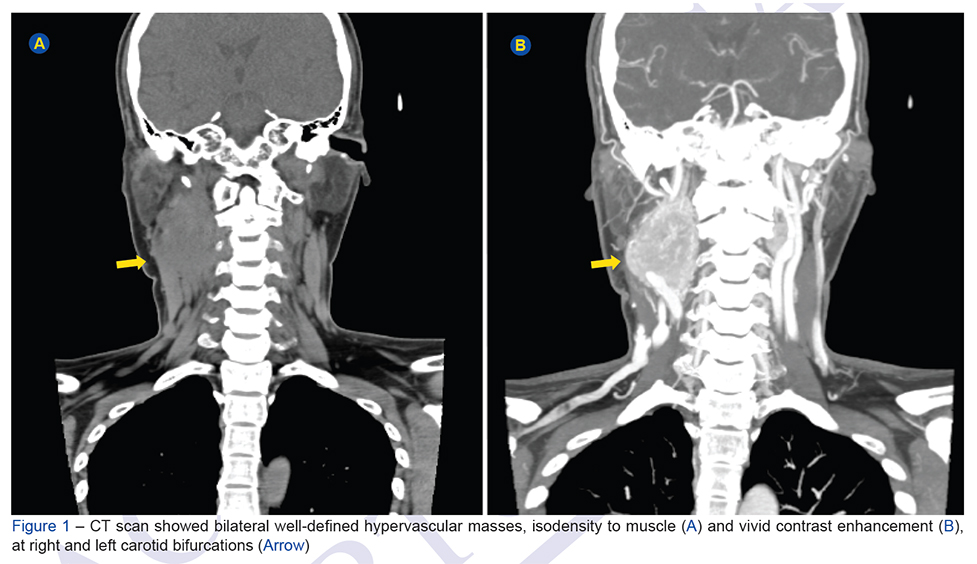

A 28-year-old woman presented with a 2-year history of a slow-growing, non-tender and pulsatile mass in the right carotid bifurcation. The computed tomography study re...